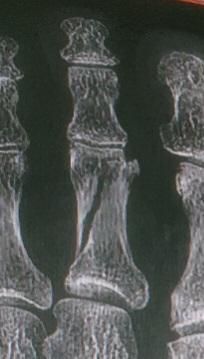

골절 사진 참부합니다. 이거 어긋난거 맞춰야되지 않나요?

저렇게 어긋나듯 삐져나왔는데요.

이거 좀.. 붙여서(?)?? 맞춰야되는거 아닌가요?

엑스레이상 뼈가 어긋나 보인다면 단순히 깁스만으로는 정렬이 안되고 변형이 남을 수 있습니다. 특히 골절이 삐져나온 듯 보이는 경우엔 정복 과정을 거쳐야 하는 상황일 수 있습니다.

시간이 지나 뼈가 어긋난 채 붙으면 이후에 교정이 더 힘들고 변형이나 기능 저하가 남을 수 있습니다 가능하다면 빠르게 다시 확인 받아 정확한 정복이 필요한 상태인지 점검하는 것이 안전합니다!